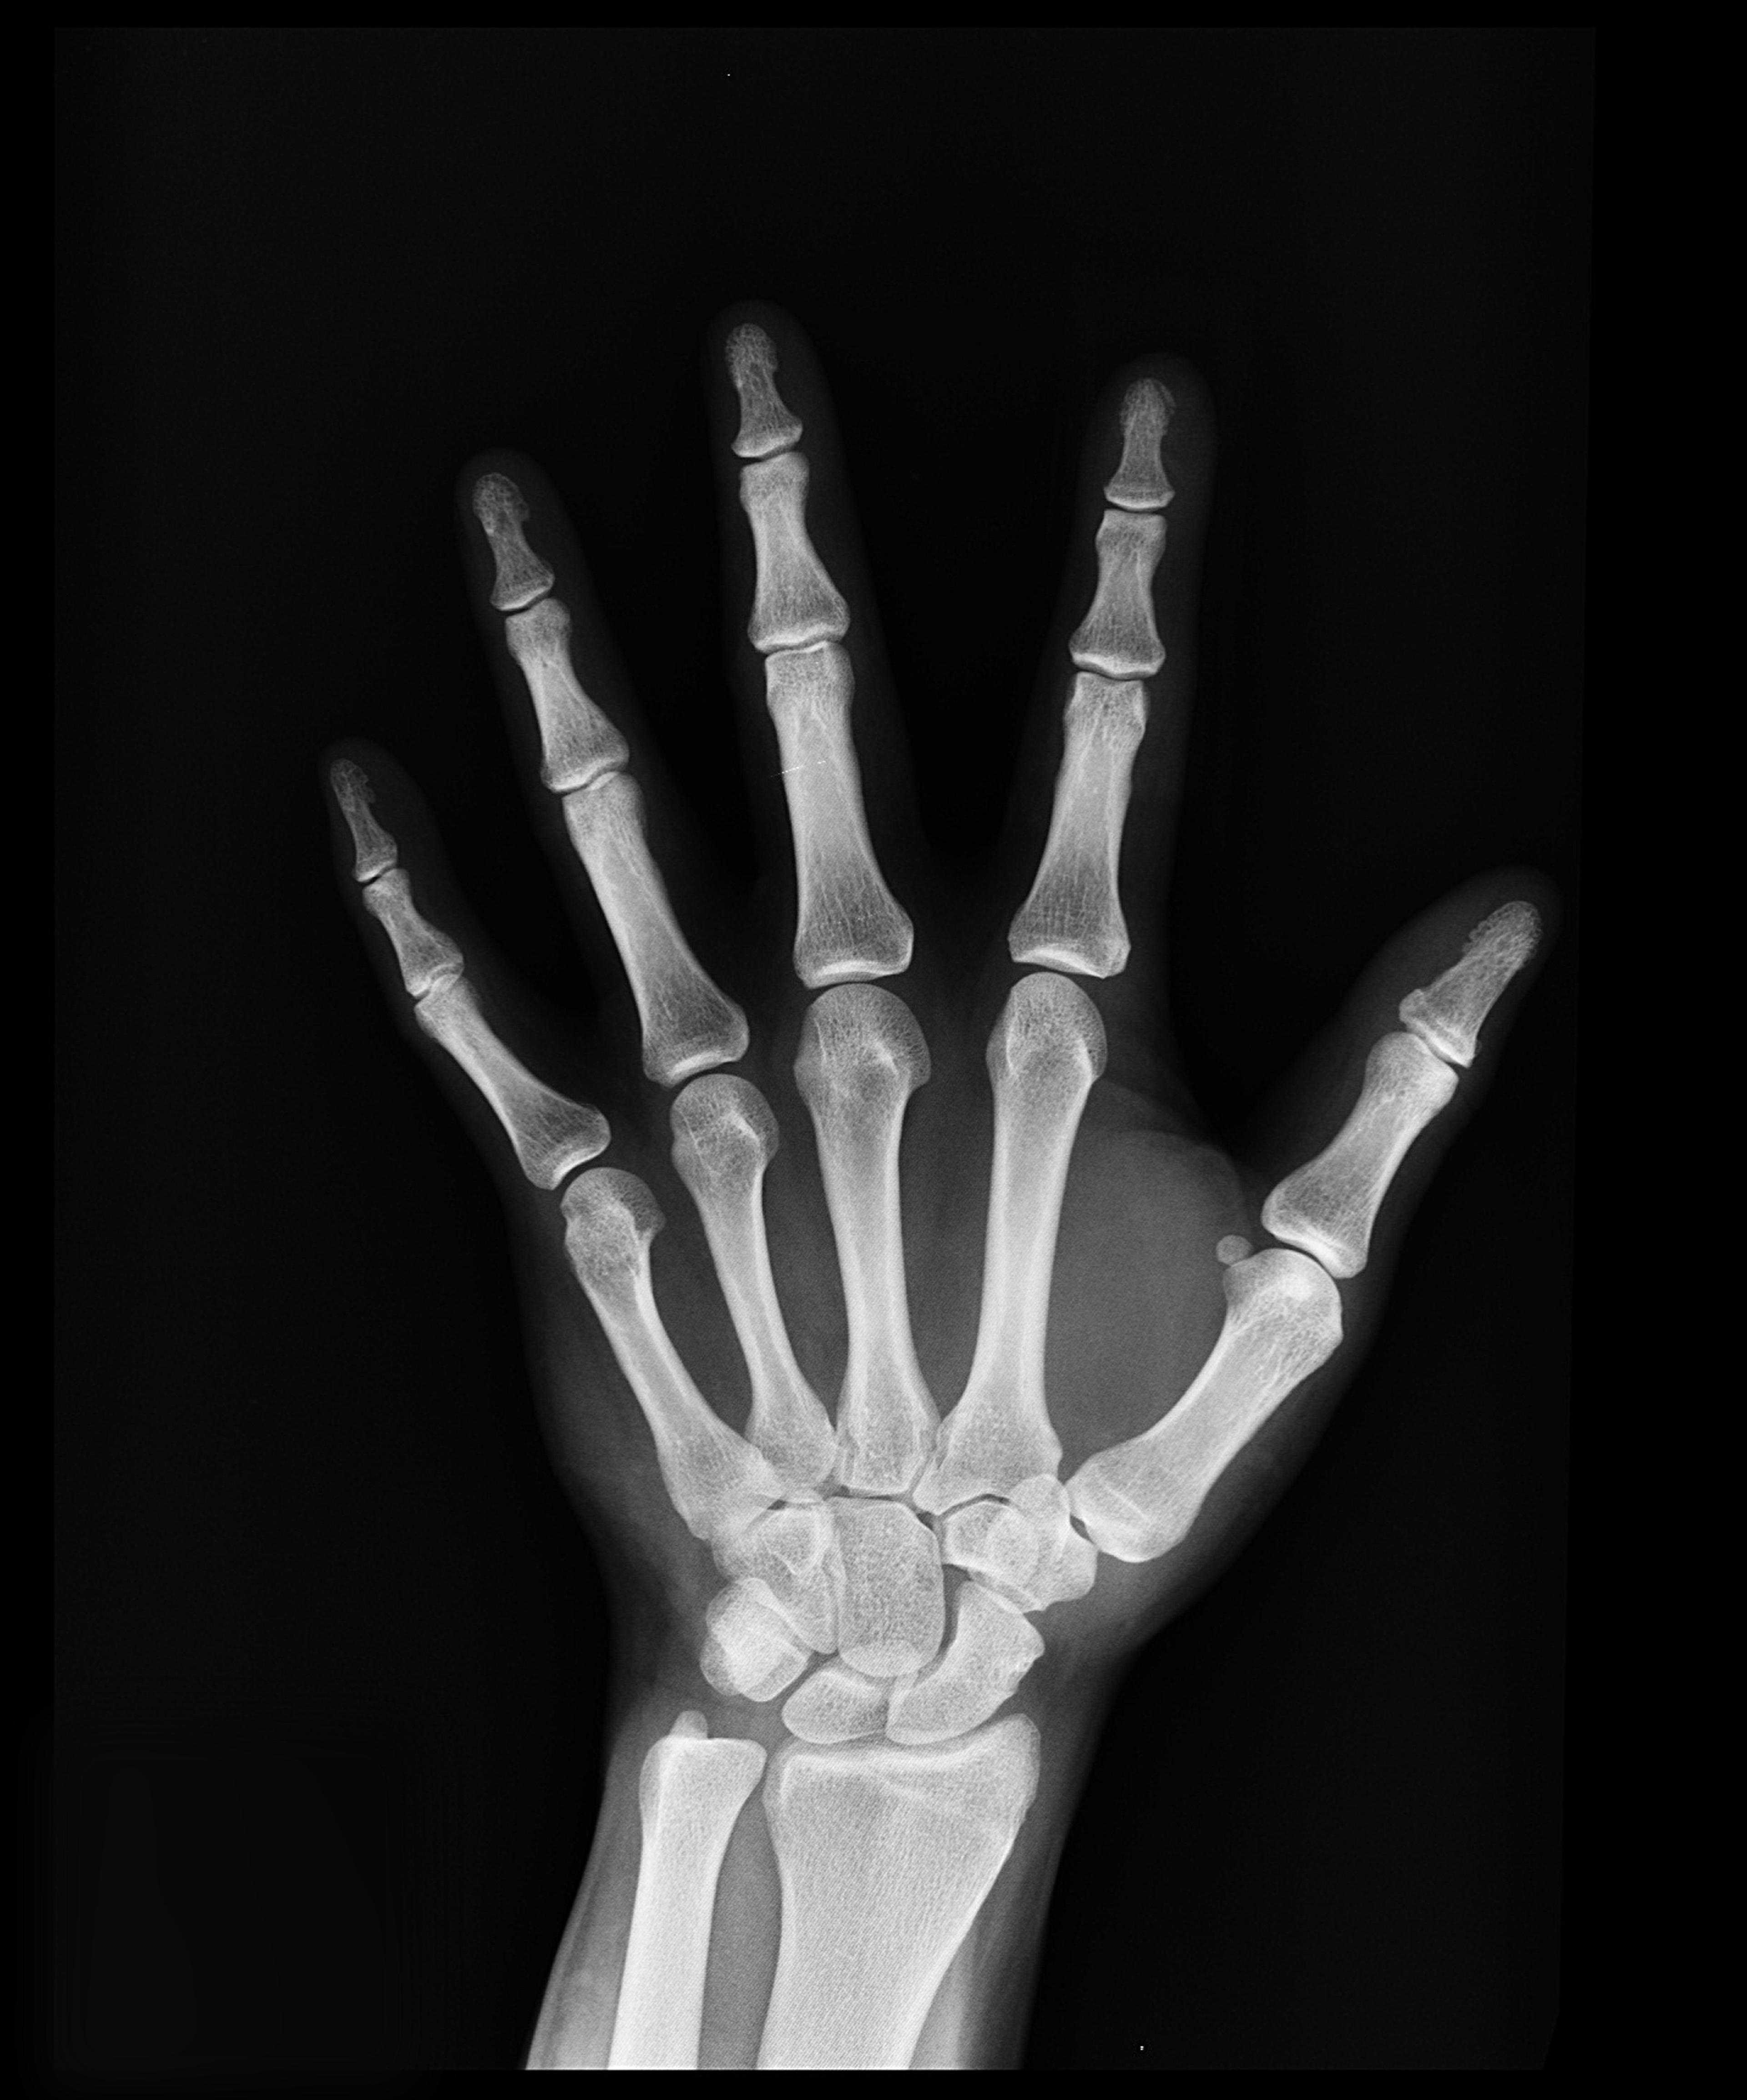

ကိုယ်ခန္ဓာရှိအဆစ်အမြစ်များအတွင်း သွေးယိုတဲ့ အခြေအနေ (Hemarthrosis) ကို ဆိုလိုပါတယ်။ ထိခိုက်ဒဏ်ရာရခြင်းကြောင့် ဖြစ်တတ်သလို ဟေမိုဖီးလျားခေါ် သွေးမတိတ်တဲ့ရောဂါကြောင့်လည်း ဖြစ်တတ်ပါတယ်။ အရိုးအဆစ်များဟာ ကိုယ်ခန္ဓာရဲ့ အစိတ်အပိုင်းတွေ ချောမွေ့စွာ လှုပ်ရှားနိုင်အောင် တည်ဆောက်ထားခြင်း ဖြစ်ပါတယ်။ အကယ်၍ အဆစ်အတွင်းကို သွေးယိုစိမ့်ခဲ့ရင် ရောင်ရမ်းခြင်း၊ နာကျင်ခြင်းတွေဖြစ်တတ်ပါတယ်။ ထိရောက်စွာ မကုသရင် အမြဲတမ်းပျက်စီးသွားနိုင်ပါတယ်။ ဘာလက္ခဏာတွေရှိသလဲ အဆစ်အတွင်း သွေးယိုတဲ့အခါ ဖြစ်နိုင်တဲ့လက္ခဏာတွေကတော့ - အဆစ်များ ရောင်ရမ်းခြင်း - နာကျင်ကိုက်ခဲခြင်း - နီရဲခြင်း - အဆစ်များကို ဖိကြည့်လျှင် လေခိုသလိုဖြစ်နေခြင်း - အဆစ်များတောင့်တင်းခြင်း - သွေးခြည်ဥခြင်း - ပုံမှန်လှုပ်ရှားနိုင်မှုမရှိခြင်း စတာတွေ ဖြစ်ပါတယ်။ ဘာကြောင့်ဖြစ်တတ်သလဲ အဆစ်အတွင်းသွေးယိုခြင်းကို ဖြစ်စေတဲ့ အကြောင်းအရာများကတော့ - ထိခိုက်ဒဏ်ရာရခြင်း၊ အရိုးကျိုးခြင်း၊ အရွတ်များစုတ်ပြဲခြင်း - ခွဲစိတ်ကုသမှုခံယူခြင်း (မှန်ပြောင်းသုံး ခွဲစိတ်ခြင်း အပါအဝင်) - သွေးယိုတတ်သောရောဂါများ (ဥပမာ ဟေမိုဖီးလျား) - သွေးကျဲဆေးများ သောက်သုံးနေခြင်း - ရောဂါပိုးဝင်ခြင်း - […]